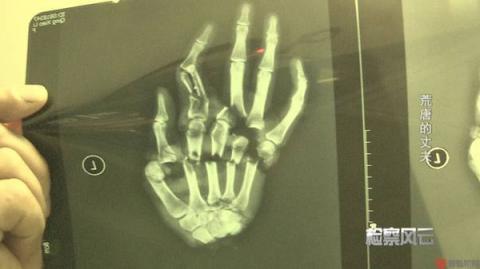

Kể lại sự việc kinh hoàng này, Anh Quân đã dành ra 15 tệ (hơn 50 nghìn đồng) mua một con dao sắc, chờ lúc vợ không chú ý đã chặt phăng bàn tay trái của vợ. Sau khi bị chồng nhẫn tâm làm hại, Vũ Thu kêu gào trong đau đớn, khi cô được chuyển đến bệnh viện đã mất rất nhiều máu. Sau 12 giờ cấp cứu, phẫu thuật ghép tay nhưng không thành công, cô đã vĩnh viễn mất đi một bàn tay.

Dù cố gắng phẫu thuật ghép tay nhưng không thành công.